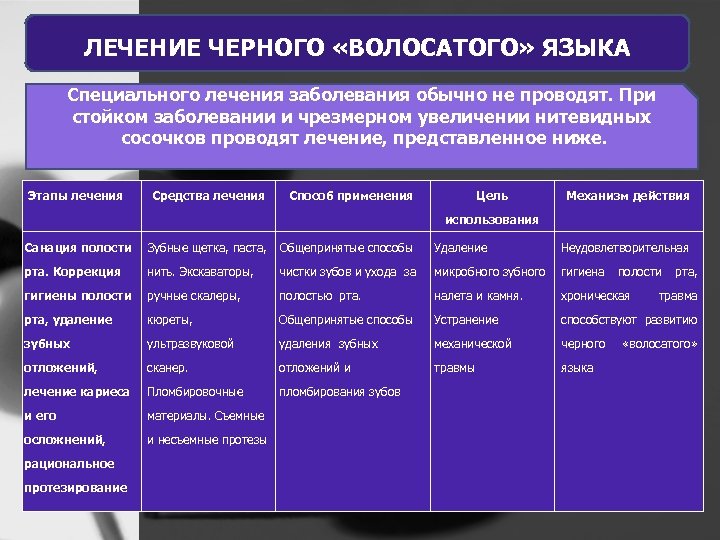

ЛЕЧЕНИЕ ЧЕРНОГО «ВОЛОСАТОГО» ЯЗЫКА Специального лечения заболевания обычно не проводят. При стойком заболевании и чрезмерном увеличении нитевидных сосочков проводят лечение, представленное ниже. Этапы лечения Средства лечения Способ применения Цель Механизм действия использования Санация полости Зубные щетка, паста, Общепринятые способы рта. Коррекция нить. Экскаваторы, чистки зубов и ухода за микробного зубного гигиена полости рта, гигиены полости ручные скалеры, полостью рта. налета и камня. хроническая рта, удаление кюреты, Общепринятые способы Устранение способствуют развитию зубных ультразвуковой удаления зубных механической черного отложений, сканер. отложений и травмы языка лечение кариеса Пломбировочные пломбирования зубов и его материалы. Съемные осложнений, и несъемные протезы рациональное протезирование Удаление Неудовлетворительная травма «волосатого»